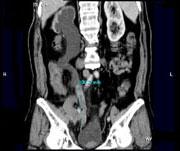

问题 男,73岁,无痛性全程血尿2个月余,CT检查如图所示,下列说法正确的是 ( )

选项 A、考虑为右侧输尿管中下段癌合并膀胱癌 B、考虑为右侧输尿管及膀胱结核 C、膀胱内可见宽基底的软组织肿块影 D、右肾及输尿管上段扩张积水 E、右输尿管中下段可见沿输尿管走行的长约10.6cm,不规则的软组织肿块影

答案 ACDE